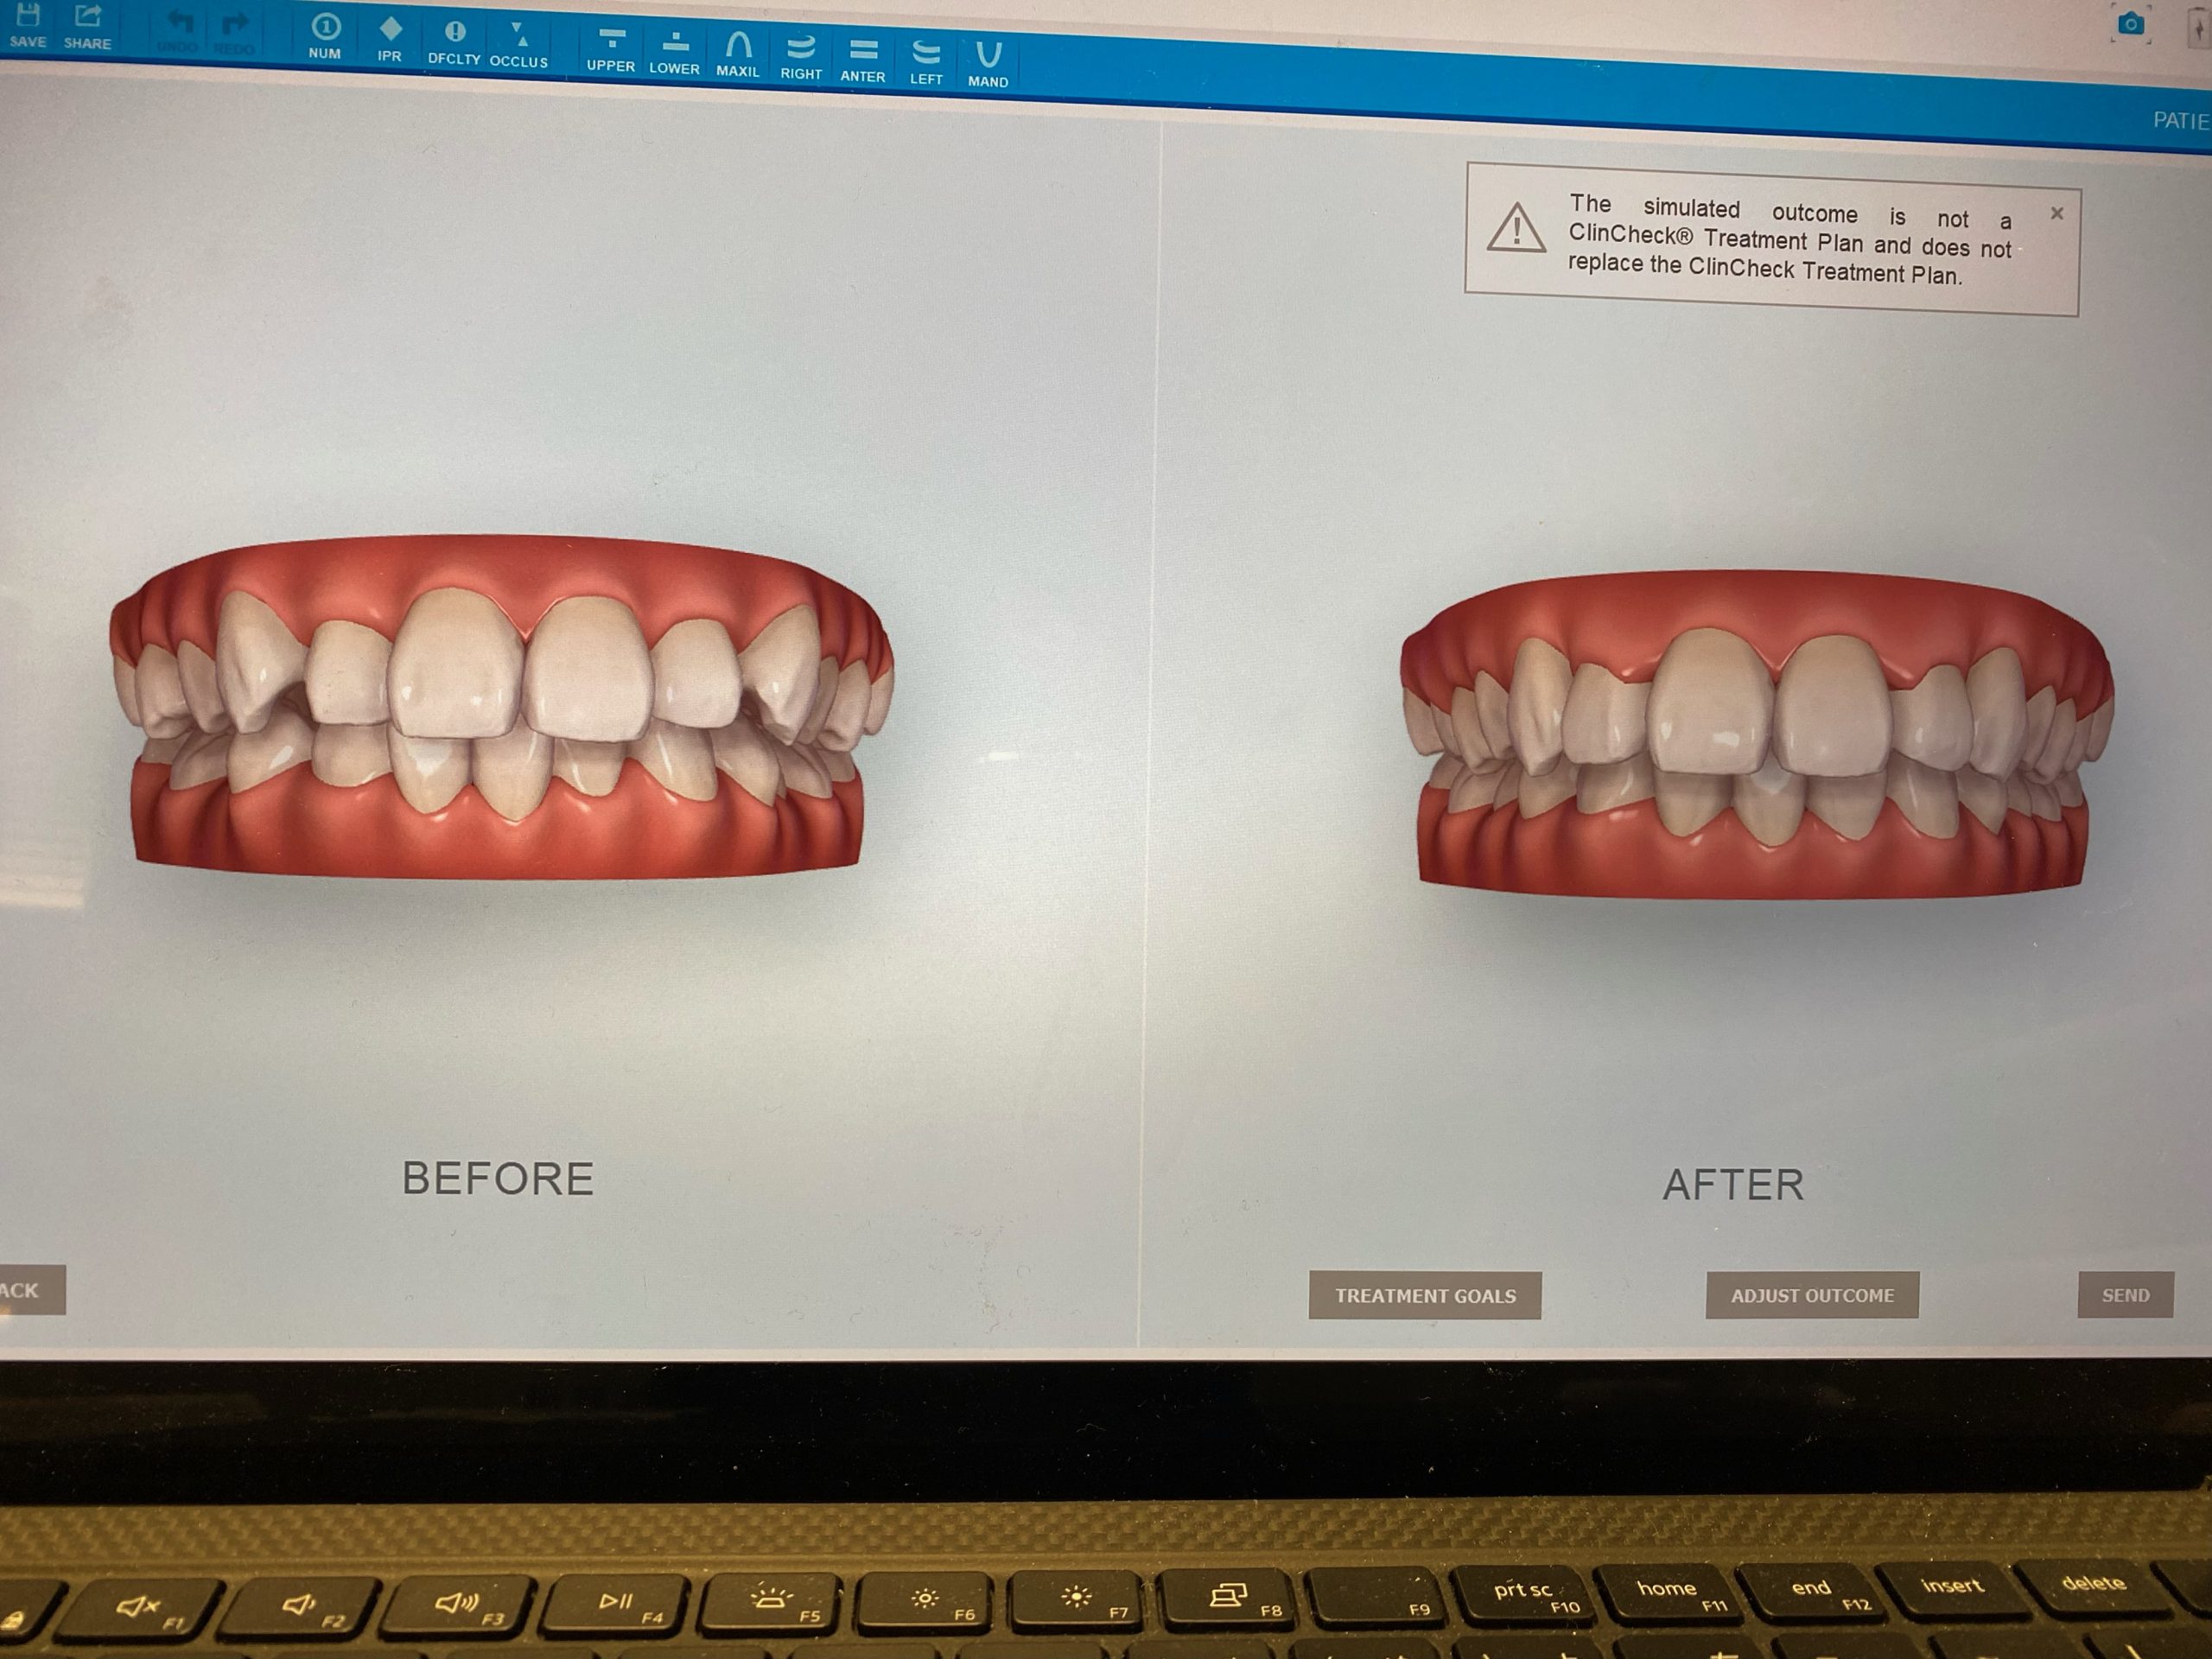

マウスピース矯正、インビザラインの矯正装置を作製する時『iTero Element(アイテロ エレメント)』という3Dスキャナーで採取しています。

この『iTero』の導入で快適にしかも精密に歯型をとることができます。

これまではシリコン印象した歯型をアメリカまで空輸していたのですが、今ではデータをインターネットで送りますので1~2週間も早く治療をスタート出来るのです。

・歯がどのように動いていくかのシュミレーションシステム

矯正だけでなく嚙み合わせが不調の方も先進的な視覚化ツールで患者様は御自身の口腔内状態についてリアルタイムで知ることができます。